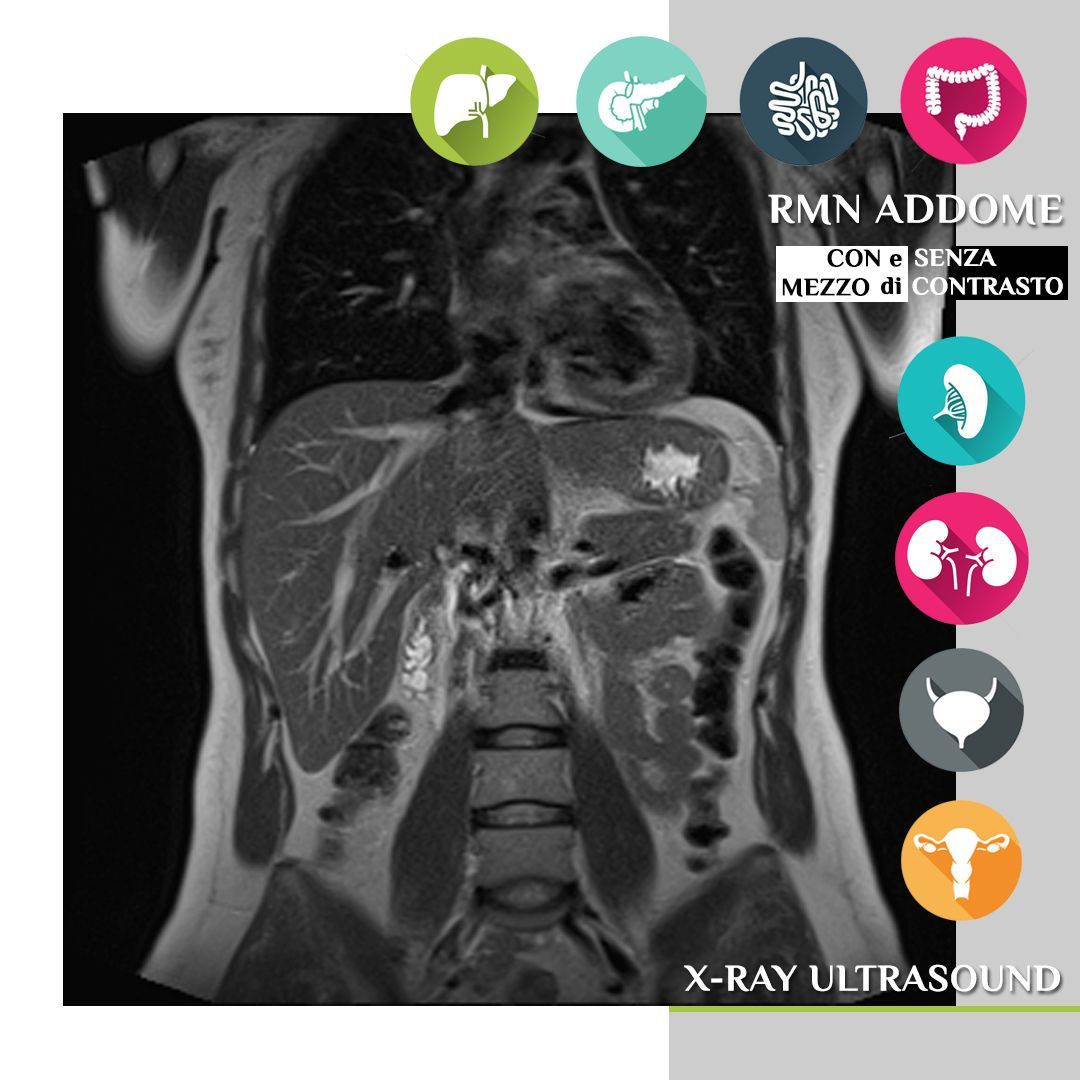

Diagnosi di patologie complesse: la risonanza Magnetom Altea è particolarmente indicata per la diagnosi di patologie complesse di diverse aree del corpo, tra cui:

- Addominale: fegato, reni, pancreas, milza, intestino